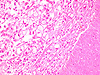

Paciente do gênero masculino, 44 anos de idade, apresenta uma lesão no palato duro e palato mole.

Paciente do gênero masculino, 21 anos de idade, apresenta uma lesão no palato duro.

Paciente do gênero masculino, 46 anos de idade, apresenta lesão no palato.

Paciente do gênero masculino, 11 anos de idade, apresenta lesão no palato.